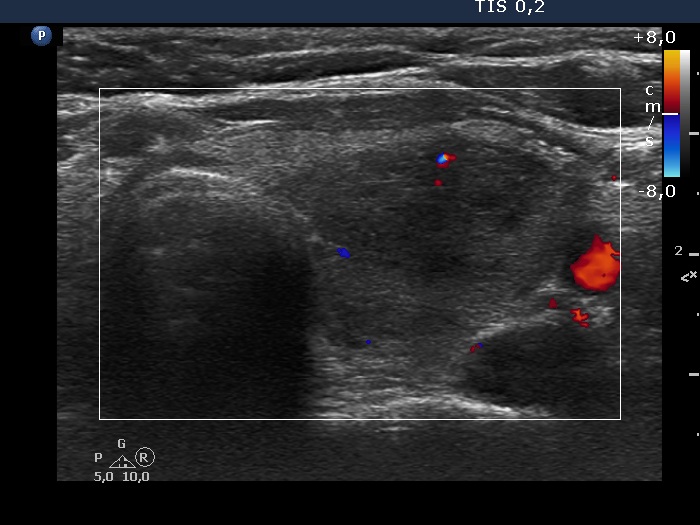

Lower part of the left lobe, transverse scan, color Doppler mode. The vascularization is decreased.